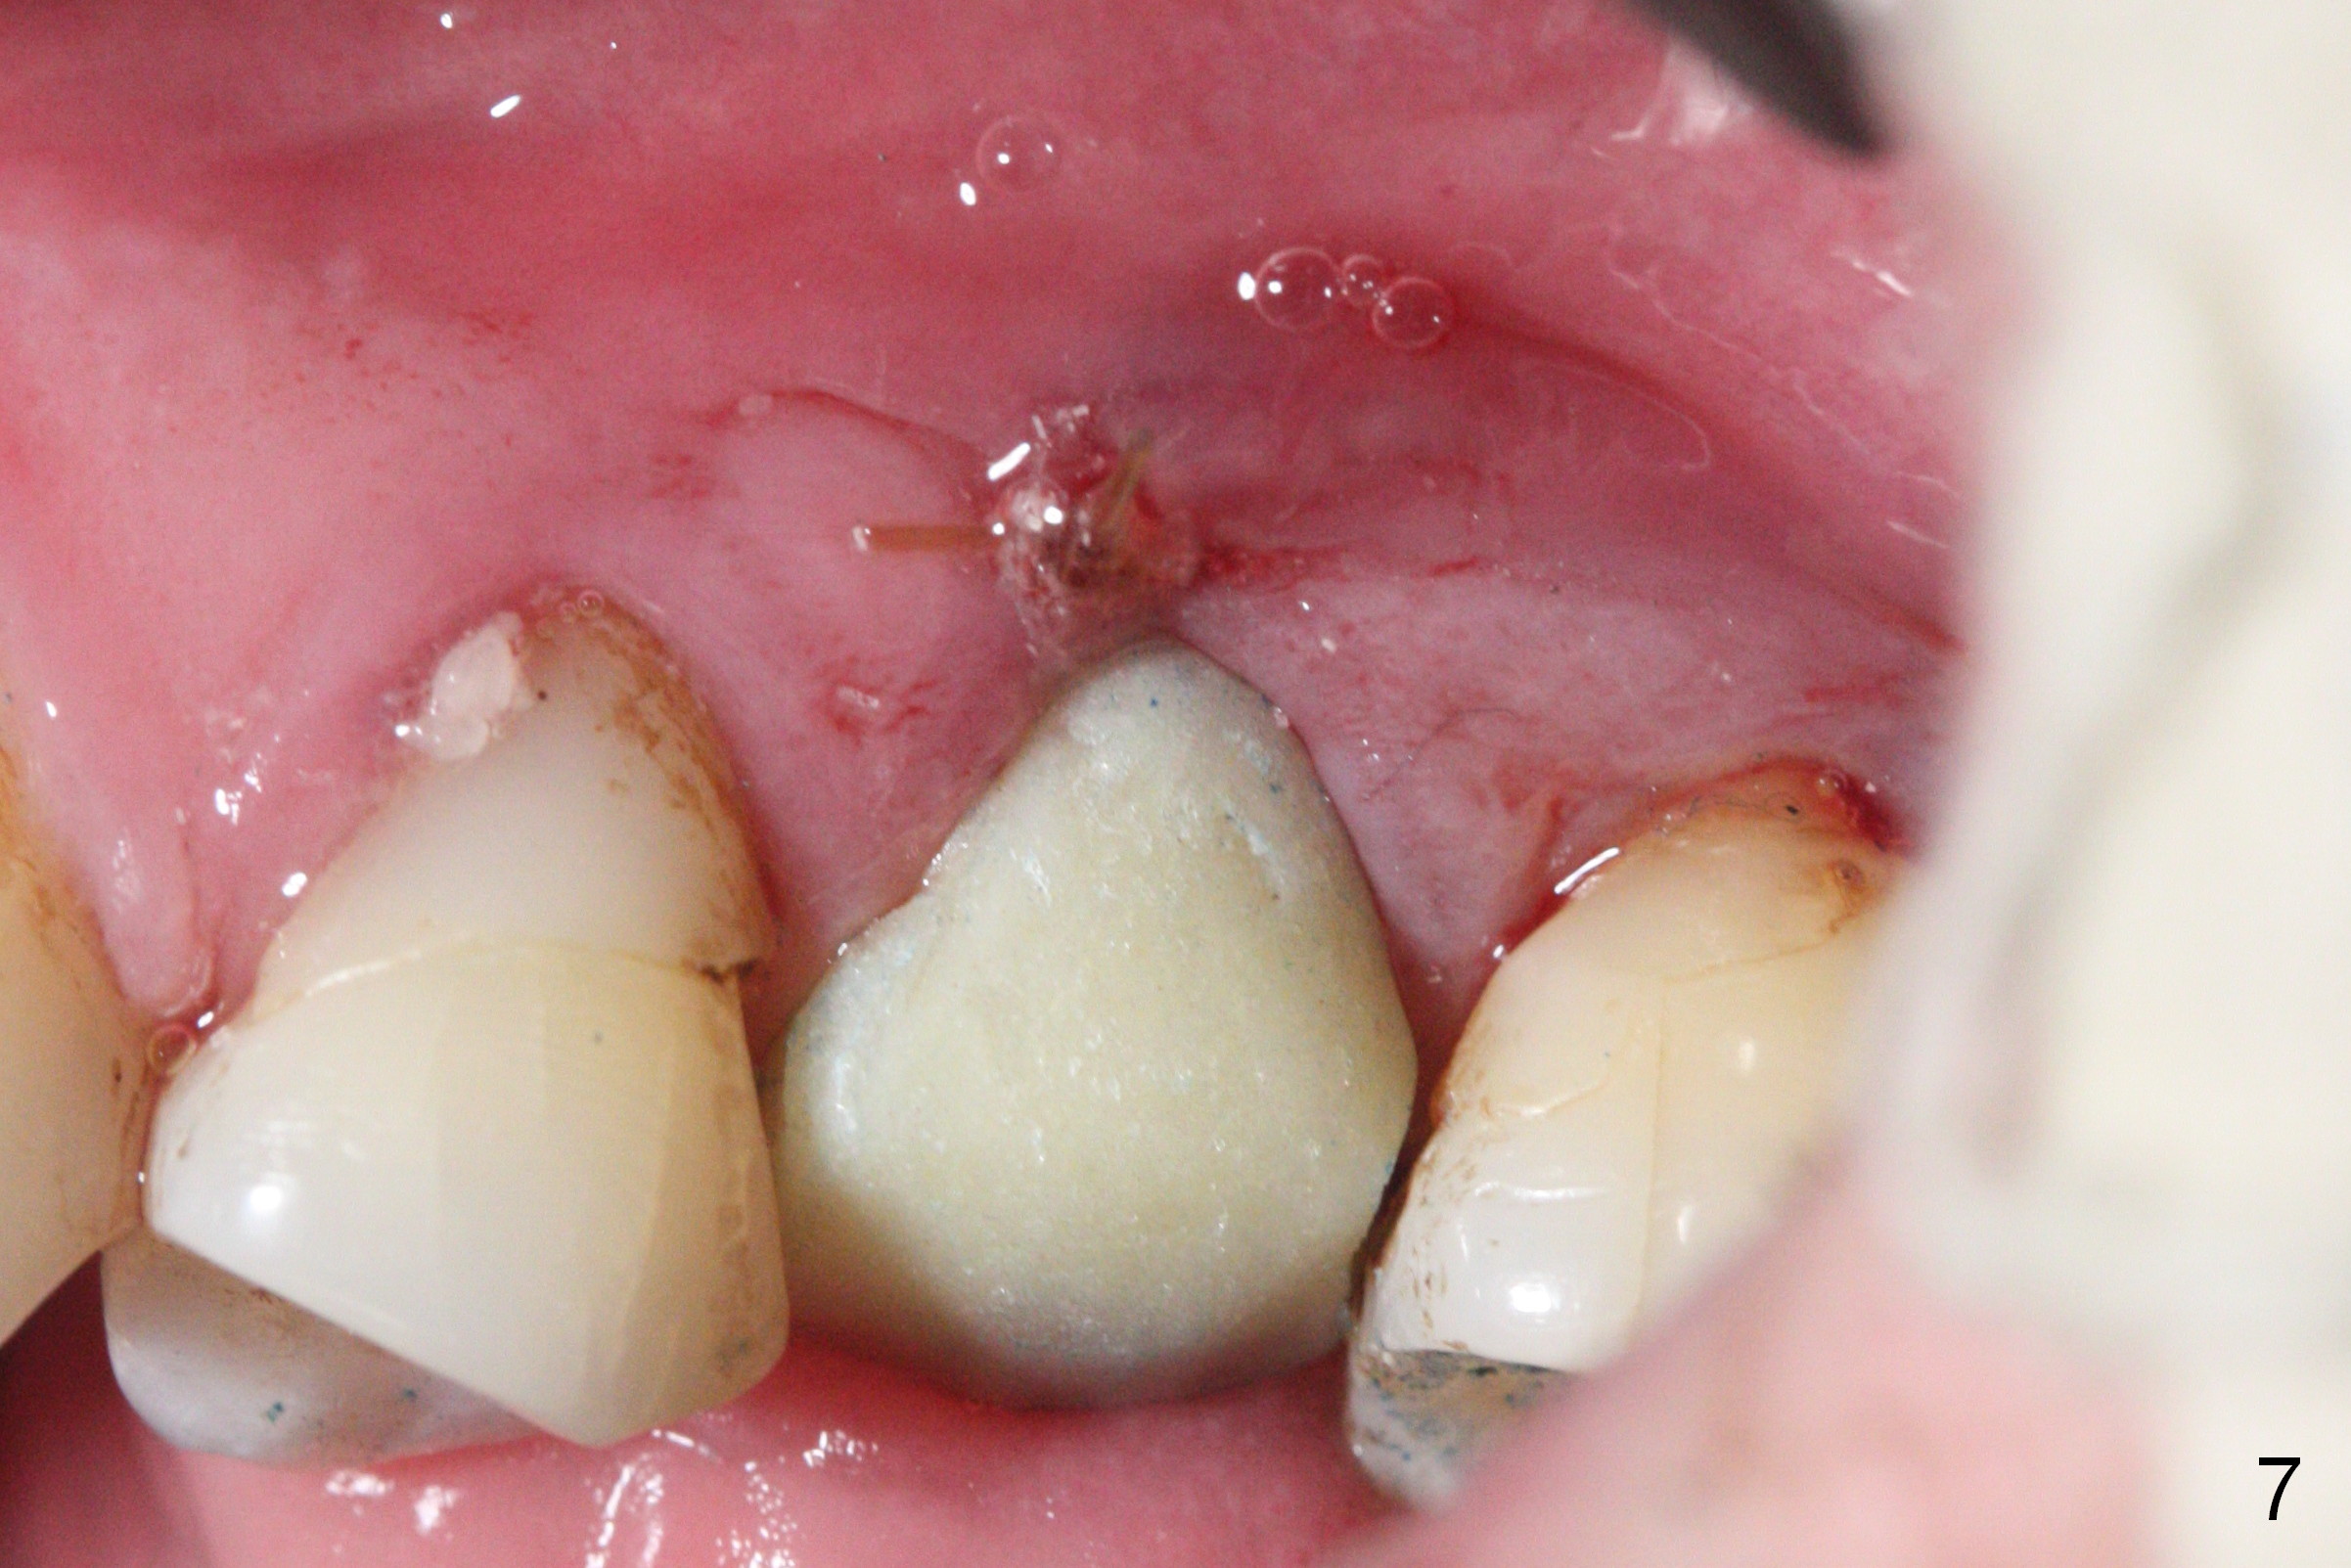

Initial osteotomy depth is 18 mm (Fig.1 green line) with 9 mm in the native bone (red line).  The bone density feels to be low.  There is at least 2 more mm bone apically (pink line).  The depth is increased by 2 mm so that when a 3.8x15 mm implant is placed, there is 10-11 mm implant/bone contact (Fig.2 red line).  There is large bony defect (Fig.3 *), which is bone grafted (Fig.4 *).  Finally a longer abutment is placed (4.5x5.5(5) in Fig.4 vs. 4.5x4(5) in Fig.2,3).  The 5 mm cuff does not look too long buccally (Fig.5) or palatally (Fig.6).   To prevent postop buccal gingival overgrowth (2), the buccal margin of an immediate provisional is subgingival (Fig.7-9 *).  Bone density between #13 and 14 appears to increase 3 months postop (Fig.10).  The implant seems to be equi-crestal (Fig.11 ^).  There seems to be more bone growth (i.e., decreasing gap) 6 months postop (Fig.12).  Impression is taken.  A crown is delivered nearly 7 months postop (08/07/2017).   While there is minimal bone loss at #13 and 15 three years and 4 months post cementation, the tooth #14 and 18 are mobile (Fig.13,14).